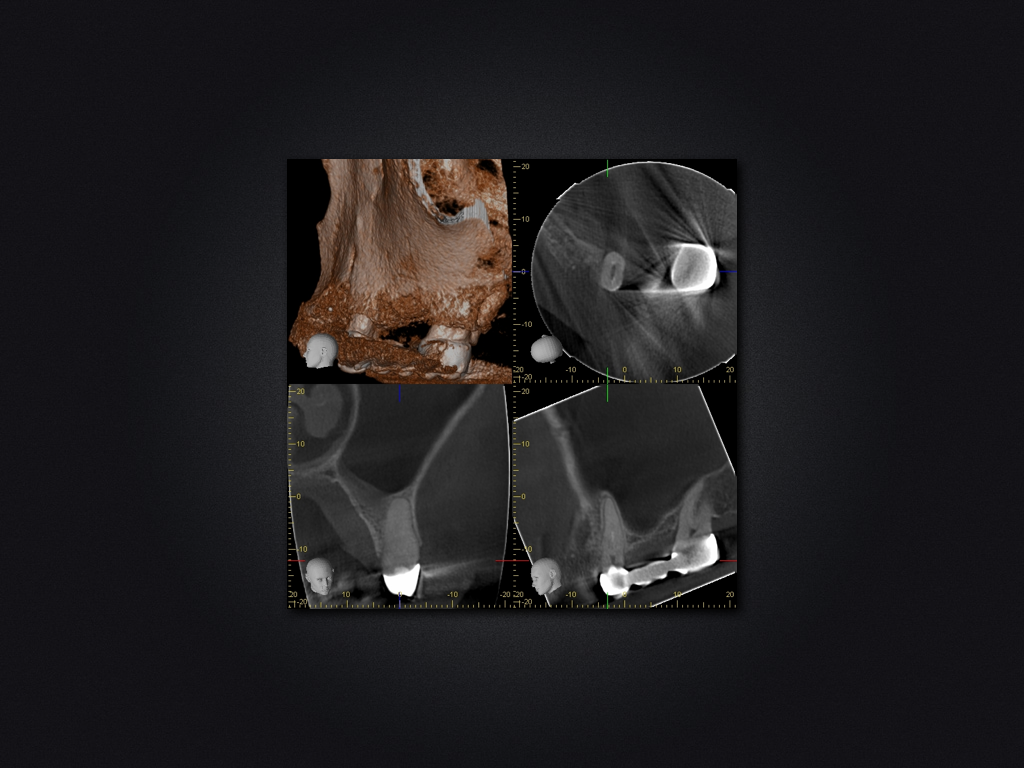

25D.003

Spülzwischenfall?